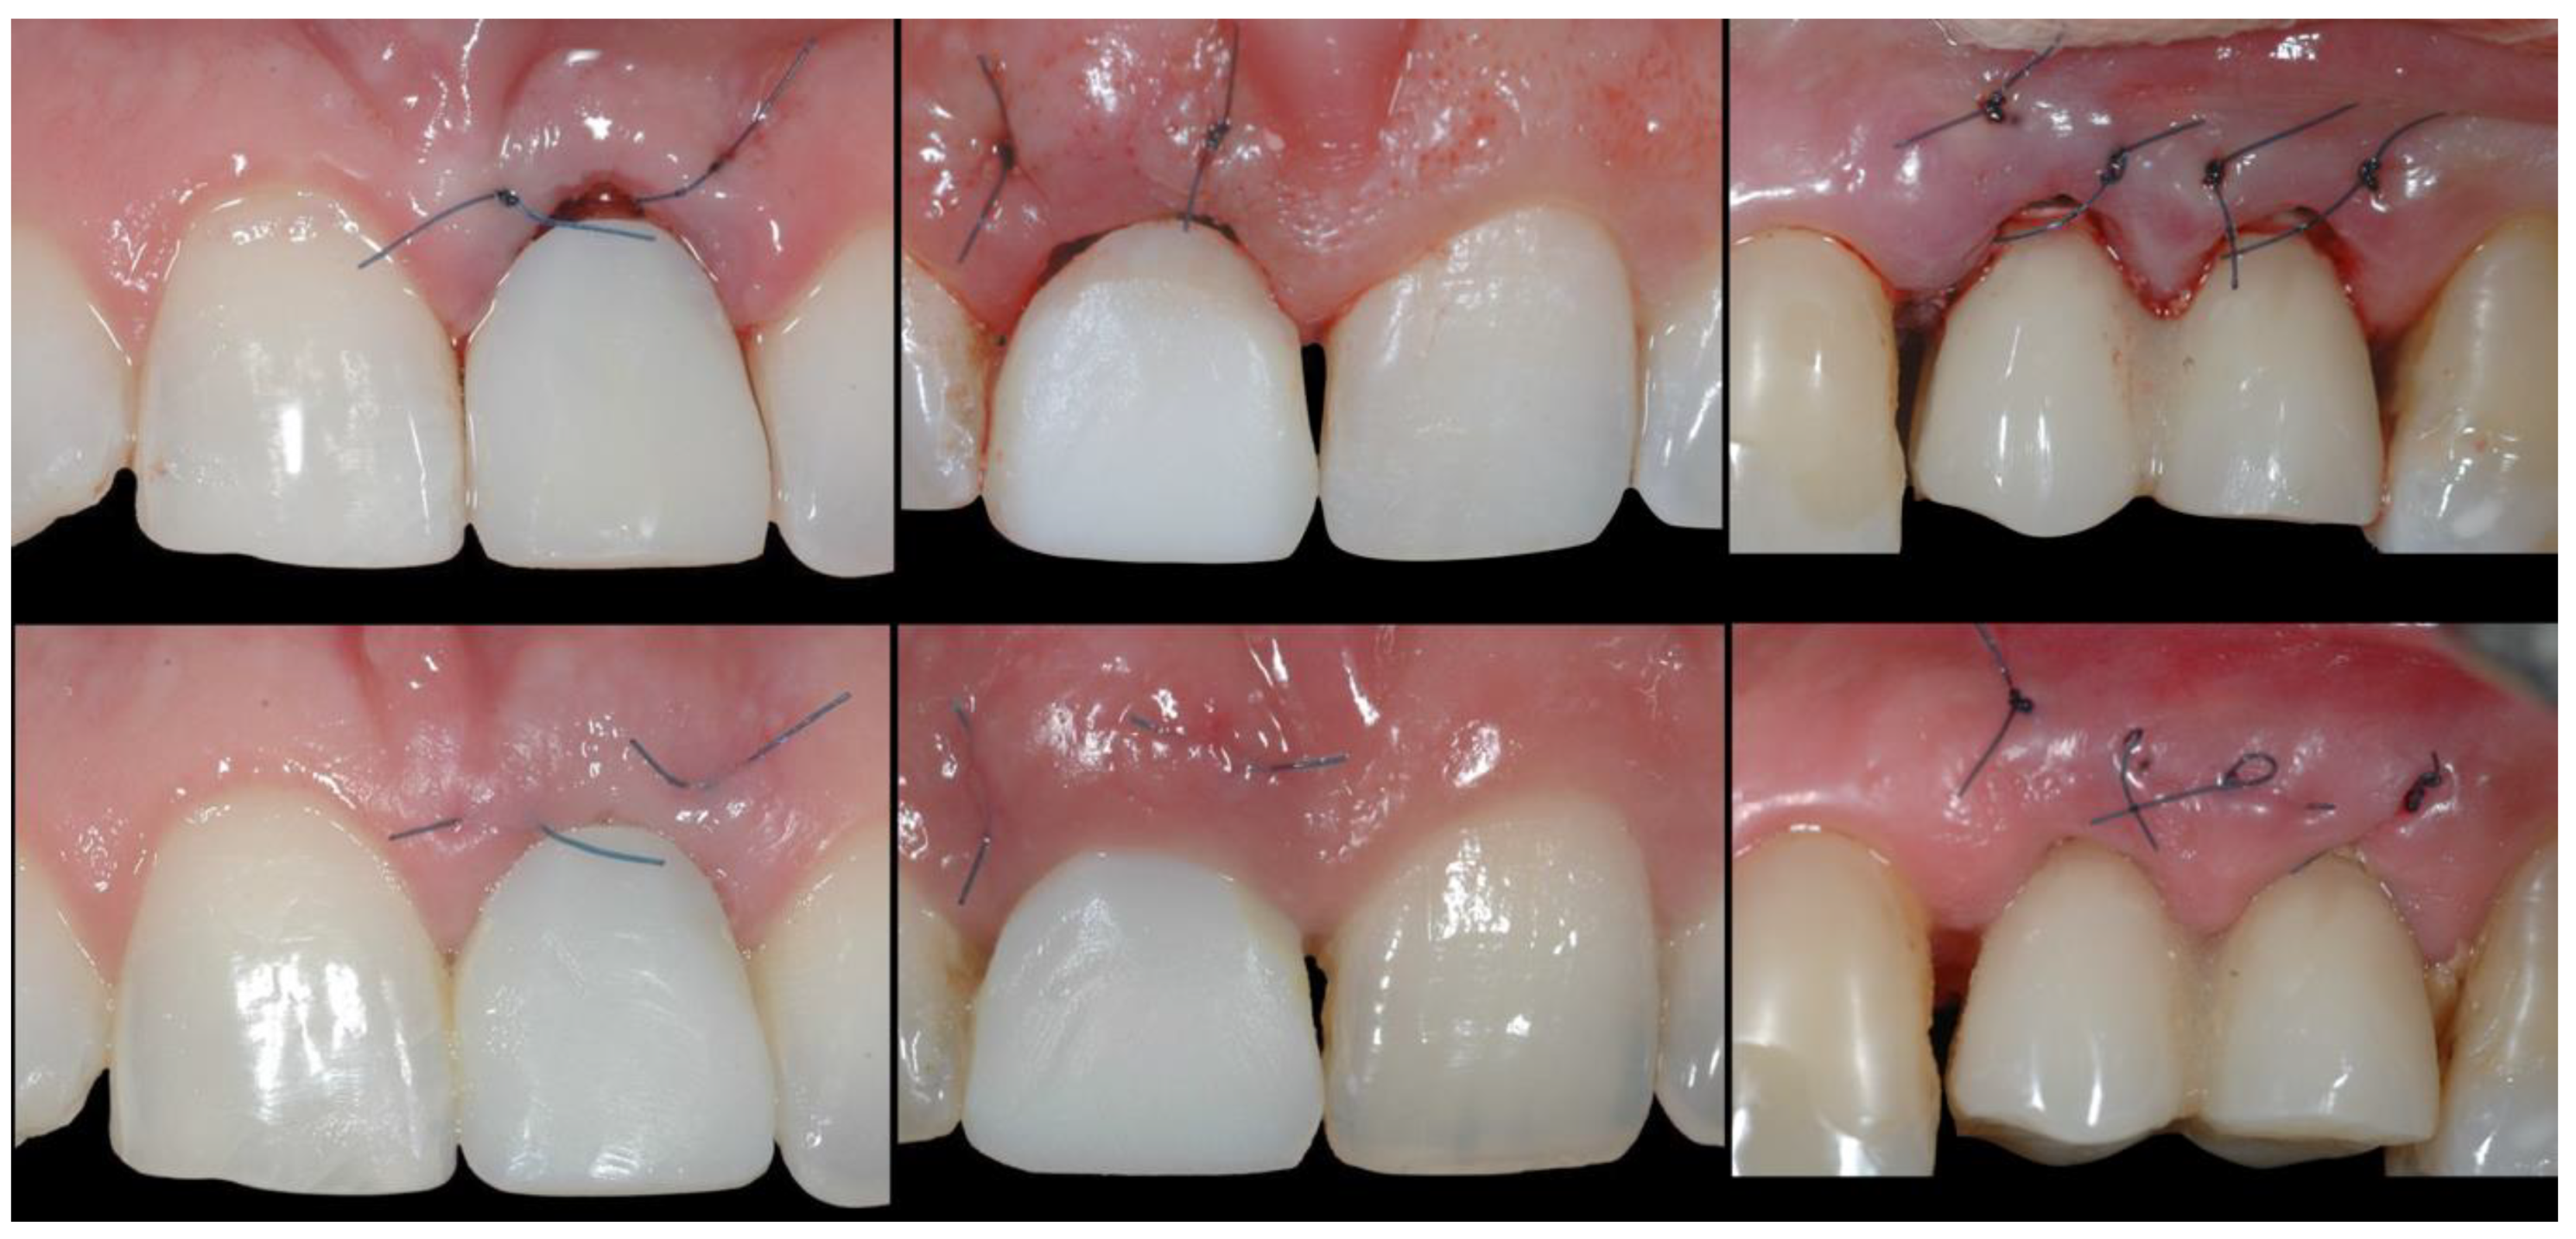

- (A)

- Supra-periosteal pouch design, demonstrating proper lateral and vertical extensions. The red lines demonstrate the pouch, while the yellow line demonstrates the mucogingival junction.

- (B)

- First abutment in place and membrane adaptation prior to BRG introduction.

- (C)

- Final relationship between first temporary prosthesis, abutment, and cervical gingival tissue.